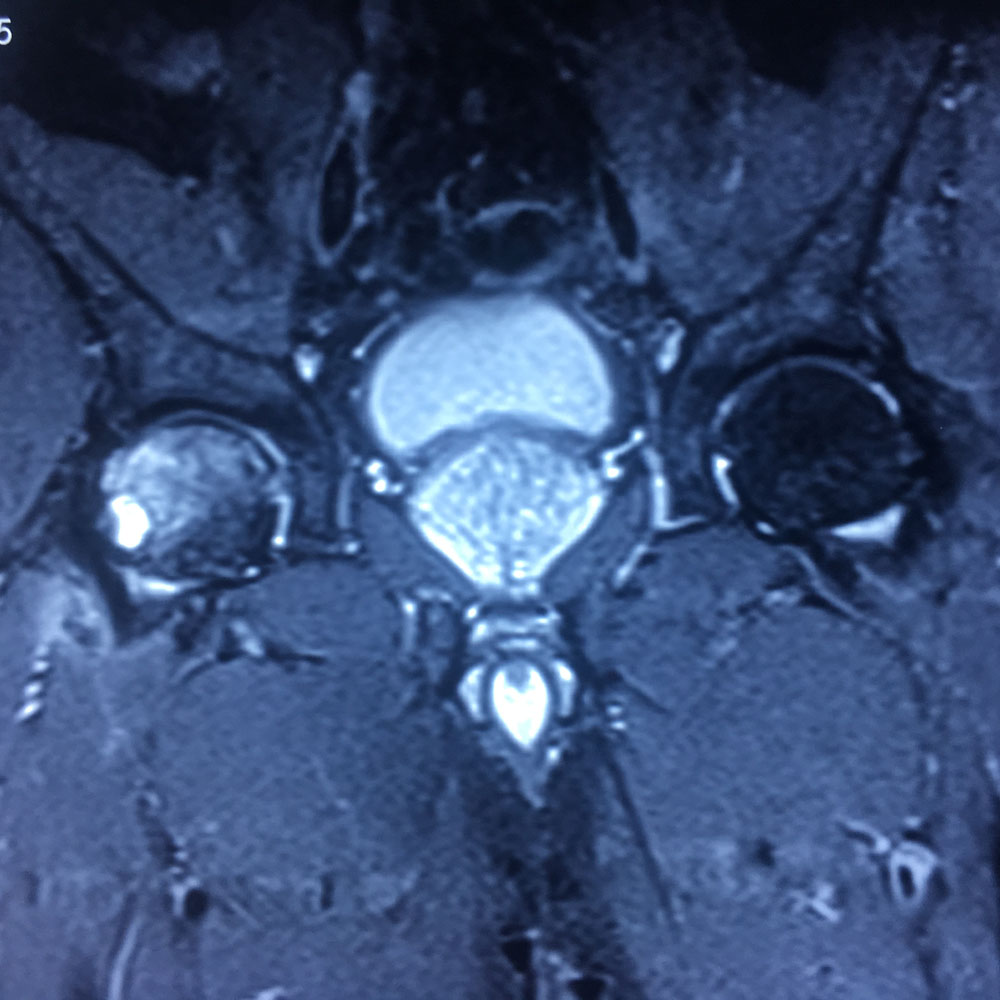

Εικόνα 4: Μαγνητική Τομογραφία του δεξιού ισχίου. Ελήφθησαν στεφανιαίες (α,β) και εγκάρσιες (γ-ιβ) διατομές σε Τ1 και Τ2 ακολουθία και τομές σε τρία επίπεδα.

Επανελέγχεται οίδημα της κεφαλής και κυρίως του αυχένα του δεξιού μηριαίου οστού. Παρατηρείται επίσης μικρή υποφλοιώδης κύστη στα πρόσθια όρια της κεφαλής διαμέτρου 8 χιλ. και ελέγχεται οίδημα των μυϊκών στοιβάδων στα πρόσθια όρια του αυχένα του δεξιού μηριαίου οστού. Συγκριτικά με τη προηγούμενη εξέταση δεν σημειώνεται ουσιώδης μεταβολή της εικόνας.